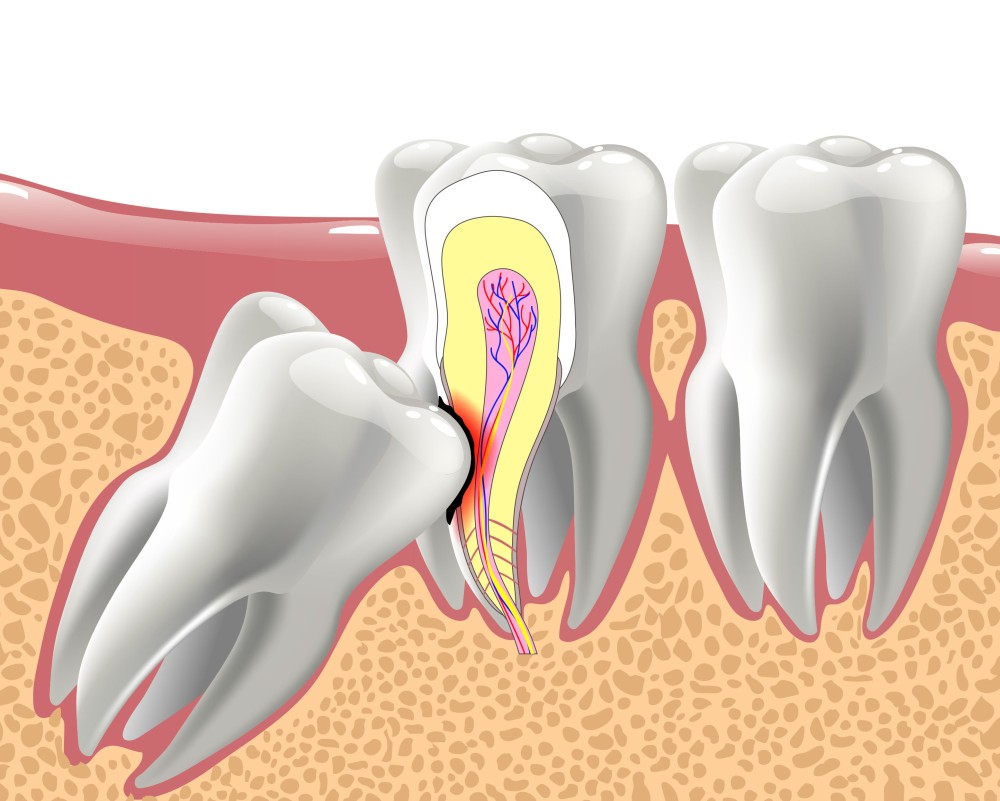

They can get partially stuck in your gums or grow at an angle. This is called an impacted wisdom tooth. Even impacted wisdom teeth don’t always need to be taken out if they aren’t causing any symptoms.

Sometimes though, the way an impacted wisdom tooth is positioned can make it easy for food and bacteria to get trapped around the gum. This can lead to swollen and sore gums (pericoronitis), tooth decay and infection. If you’re having problems such as these, your dentist may recommend taking the impacted tooth out.

If your dentist thinks there’s a high risk of the nerves around your tooth being damaged, you may be offered a coronectomy. This is a procedure where the crown of the tooth is taken out but some of the root is left in place. This may help to reduce the chances of nerves around your tooth being damaged.